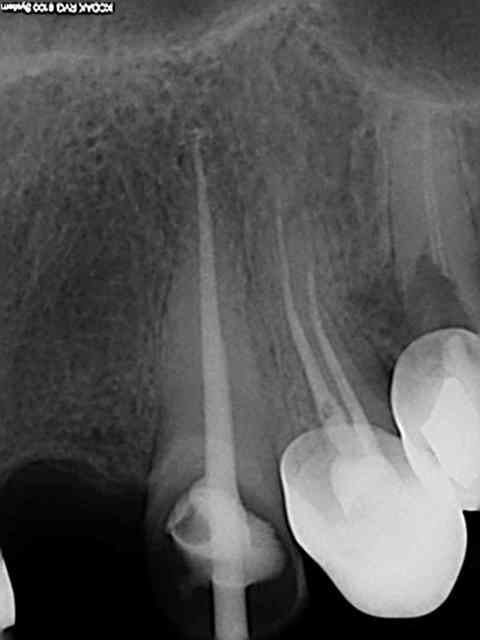

Tiens les endos de la semaine, que d'apex défoncés !-))

La 47 en fin le distal est obturé au système B (bouchon apical) et au mac spaden pour la partie coronaire, tu vois la différence à la radio ? Alors l'apex défoncé il faut avoir l'oeil ! peut etre mais à 25 centièmes et à conicité 6 %........-))